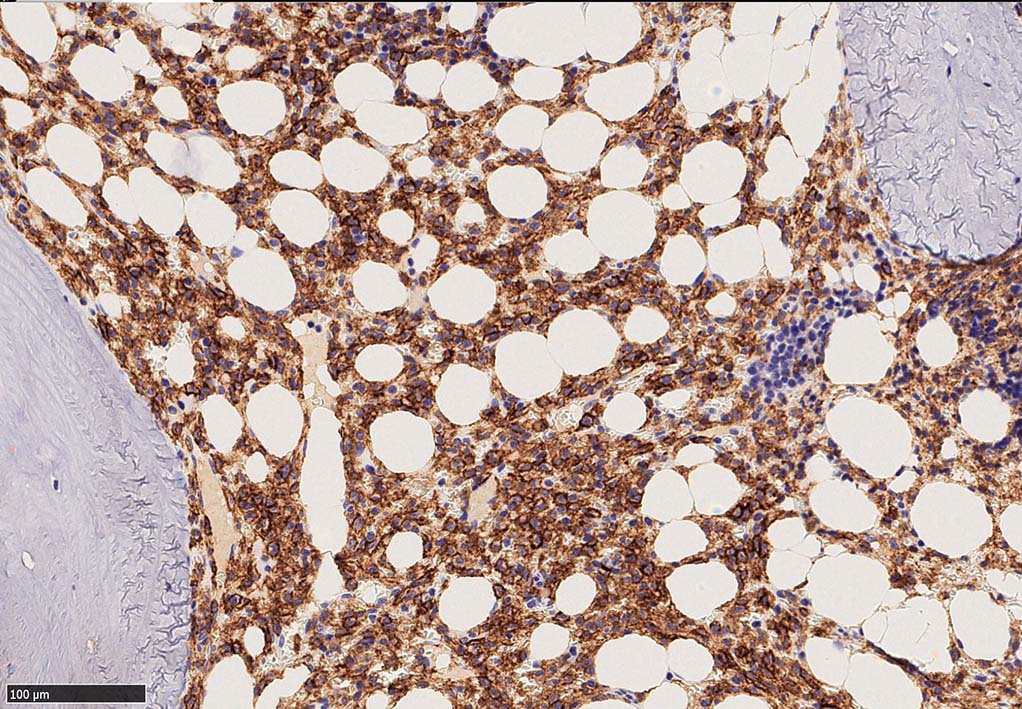

Hairy-FCM のコピー.jpg ASD-up-PAX5ok.jpg びまん性にPAX5陽性の小型B-cellsが増殖している.

増殖細胞はCD20(相変わらずべったり染まる), CD19, PAX5陽性 CD25陽性.